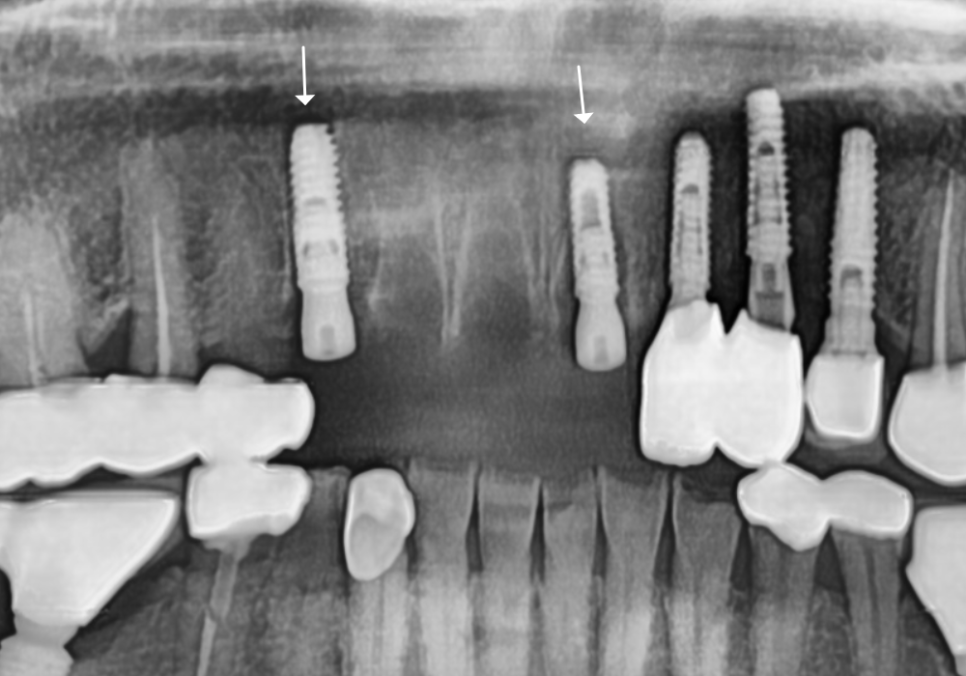

이때 저는 환자분의 심리적인 부담과

비용적인 고민을 조금이라도 덜어드리기 위해,

251023

앞니 4개를 발치하더라도

임플란트는 단 2대만 식립하는 계획을

제안해 드렸어요.

다행히 다른 곳은 뼈 상태가 양호해,

염증으로 뼈가 녹았던 송곳니 부위에만

꼭 필요한 만큼의 뼈이식을 병행하기로 했습니다.